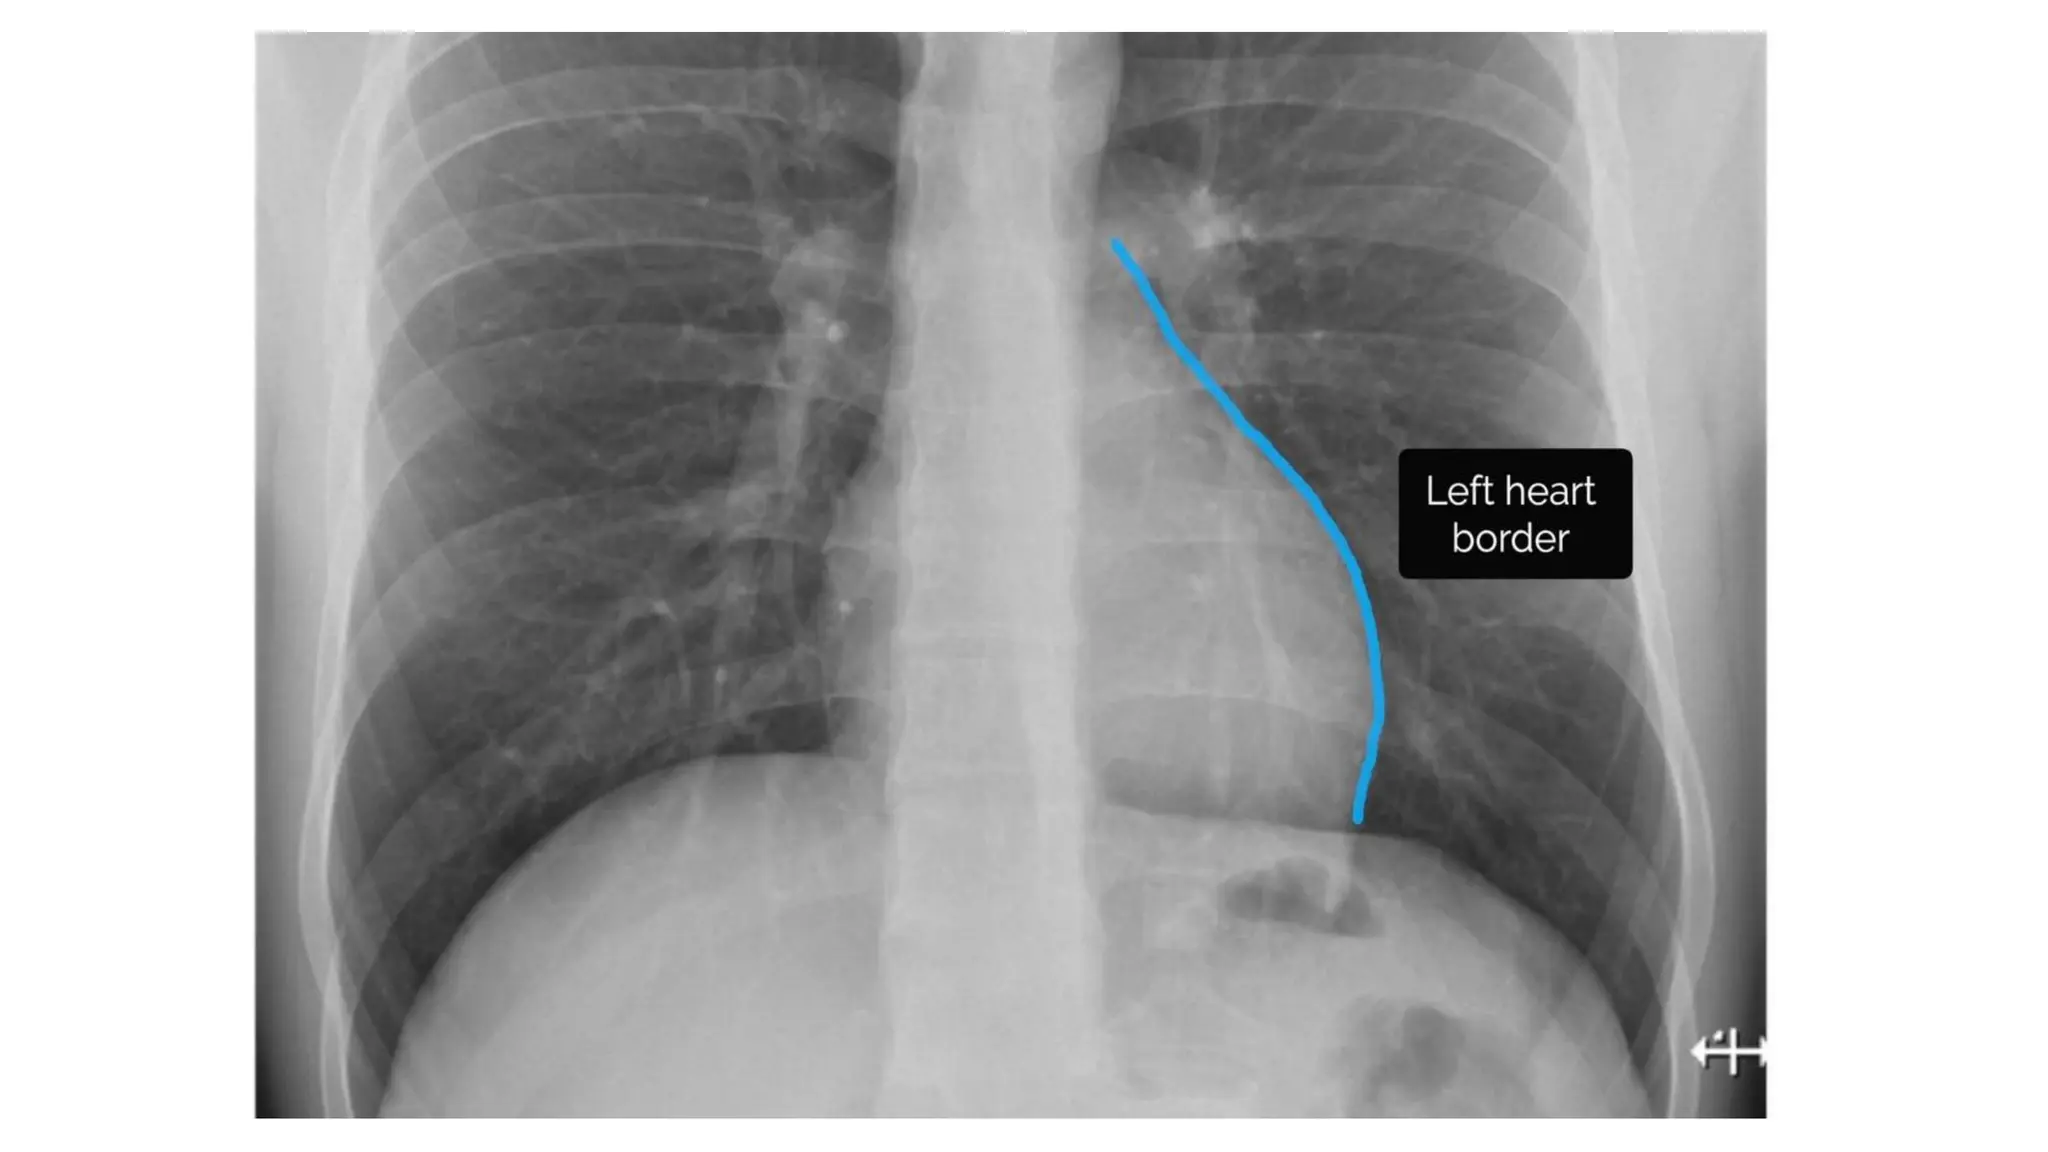

Cardiac borders

• In healthy individuals the borders

of the heart should be clearly

visible & well-defined.

Cardia • Assess thefollowing: Cardiac size Cardiac borders

• 47.

Cardiac borders • Inhealthy individuals the borders of the heart should be clearly visible & well-defined.